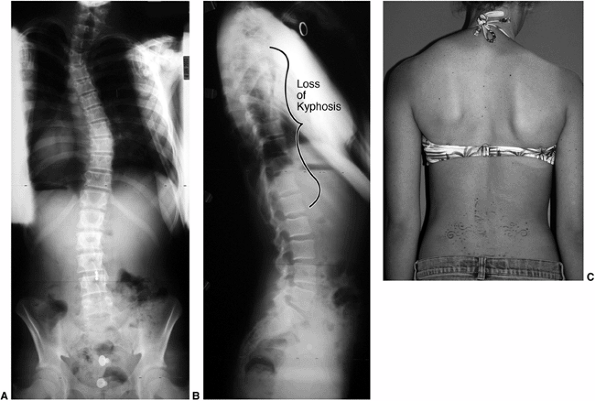

Figure 18.1 A:

This 16-year-old girl with severe scoliosis refused early treatment and had severe progression. Her clinical examination demonstrated marked trunk and rib deformity, and she had reduced pulmonary function. B: The posteroanterior radiograph demonstrates a right thoracic curvature of 125 degrees. With proper diagnosis and early treatment, deformity such as this should be completely avoidable in AIS.  |